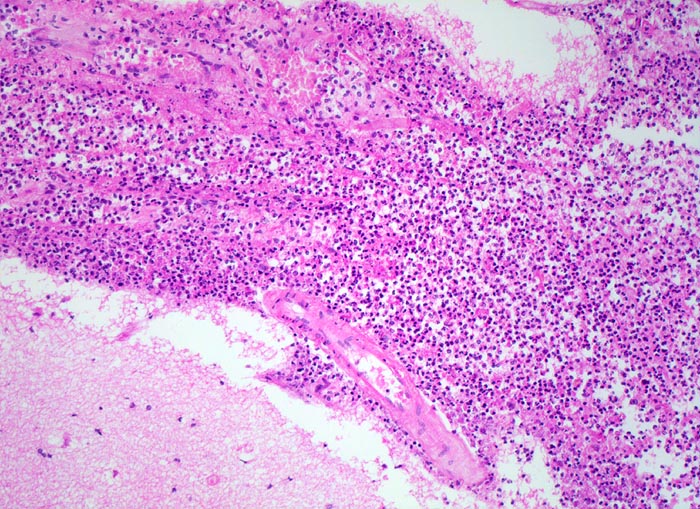

Morphologie:

Der makroskopische Befund bei bakterieller Meningitis kann sehr diskret sein. Die meningealen Gefässe sind hyperämisch und die Hirnoberfläche wird von einem grüngelben Eiterbelag bedeckt (eher basal bei Hämophilus influenzae, eher über der Konvexität bei Pneumokokken=Haubenmeningitis). Histologisch ist der Subarachnoidalraum mit Eiter gefüllt. Bei weniger schweren Fällen finden sich die neutrophilen Granulozyten bevorzugt um die leptomeningealen Gefässe.